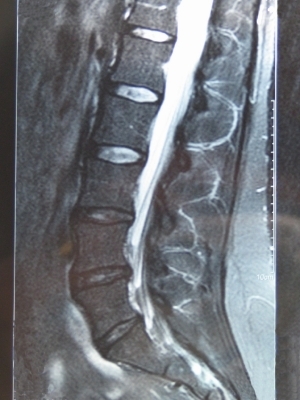

ДИАГНОСТИКА

Изучение истории болезни и медицинский осмотр не проводятся. МРТ или КТ Миелограмма необходимо для установления диагноза.

Медицинские процедуры, проводимые при заболевании межпозвонковая грыжа: Магнитно-резонансная томографияЛЕЧЕНИЕ И ПРОФИЛАКТИКА